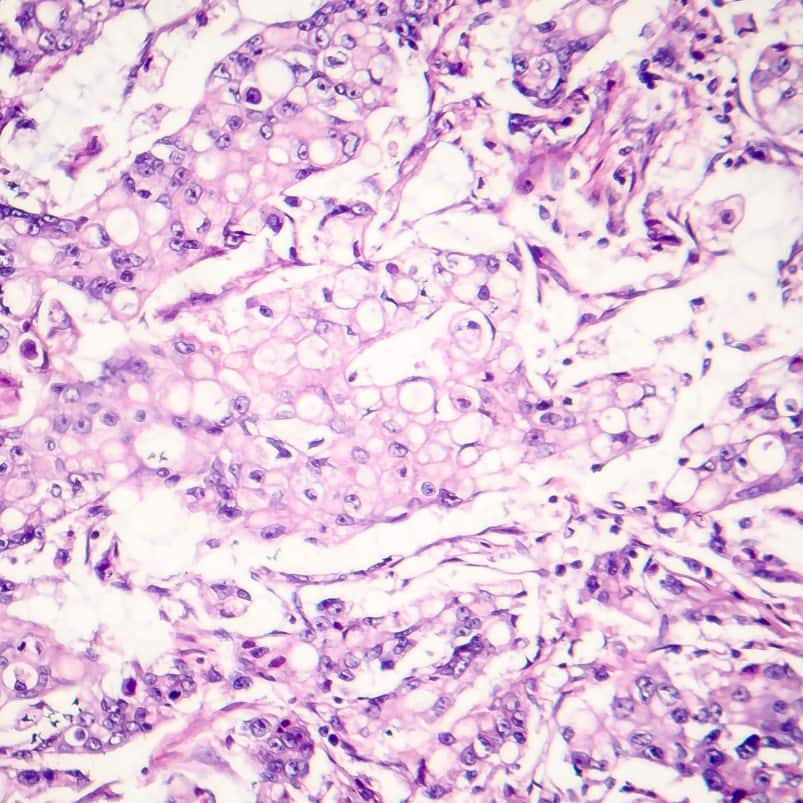

Precision’s on-site pathologists offer a breadth of customized solutions

Our on-site pathologists are solely dedicated to research, providing complete quality control and in-depth analyses of your samples. Supporting all areas of clinical research – biomarker discovery and evaluation, companion diagnostics development, and in vitro diagnostics (IVD) development, including clinical trial work, regulatory support, and optimizations.

Supporting sample characterization and assay validation, orthogonal data, and reproducibility studies

- Leverage large, comprehensive clinical pathology datasets for multiple disease indications to reveal biological complexity in each tissue section

Customized pathology annotation services to get the most out of your tissue samples

- Board-certified pathologist scoring, review, and annotation of tissues and cells